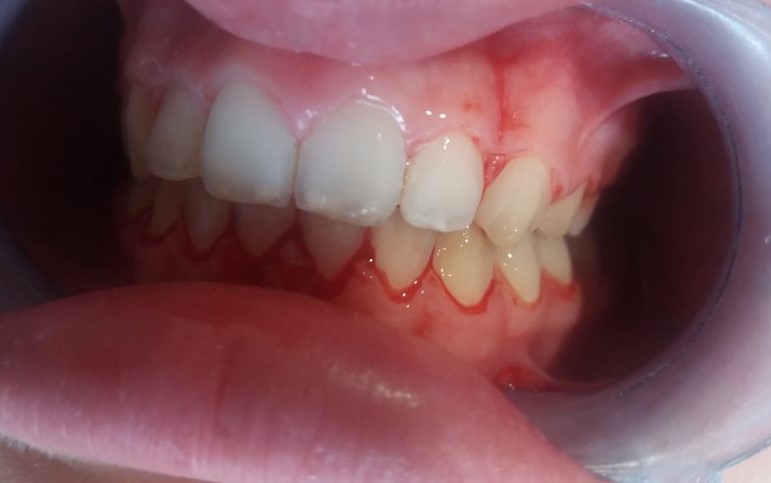

Vamos a ver el tratamiento de ortodoncia de un paciente de 11 años de edad en el que se observa una clase II de tipo dento-alveolar. Tiene un perfil de ligera protrusión del maxilar superior y retrusión de la mandíbula. Los incisivos inferiores llegan a contactar con el paladar superior pero muy hacia atrás. Esto le da un perfil de pájaro. Siendo la causa diversa en las que se mezcla diferentes parafunciones como interposición del labio inferior entre los dientes incisivos superiores e inferiores, o también interposición lingual al tragar etc. Es decir son los músculos (labio, lengua etc.) con sus malos hábitos los que producen las mal oclusiones e incluso trastornos del desarrollo óseo maxilomandibular normal. Es decir los músculos de la cara son los arquitectos de los huesos faciales, en este caso que exponemos para mal.